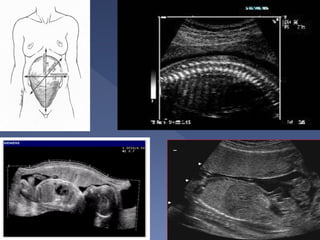

 Most reproducible/accurate

 Technique(4 quadrant technique)

Divide the uterus into four quadrants using the

linea nigra as the vertical axis and the

umbilicus as the horizontal axis.

 Linear transducer head placed along mother’s

longitudinal axis and held perpendicular to the

floor in the sagittal plane.

The pocket with the largest vertical dimension

is measured in each quadrant.

Sum of all four measurements = AFI